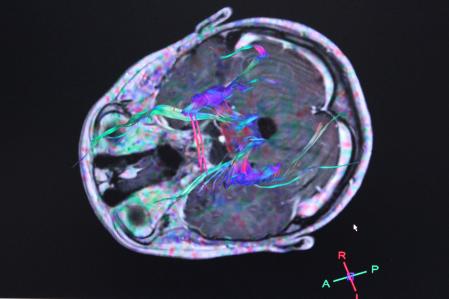

Son muchas las voces que se han pronunciado sobre la longevidad humana en distintos ámbitos, entre ellos Richard Restak. El neurólogo, expresidente de la Asociación Estadounidense de Neuropsiquiatría, concedió una entrevista al periódico británico The Guardian, en la que indagaba en una serie de patrones de comportamiento. Estos aparecen vinculados con el deterioro cognitivo a partir de los 60 años, y pueden ser la primera pista para detectar una enfermedad neurodegenerativa, como podría ser el alzhéimer.

“Si olvidas dónde dejaste las llaves del coche y finalmente las encuentras dentro de la nevera, o la abres y está el periódico, eso es el primer síntoma de algo grave: eso va un poco más allá del olvido”, dejaba claro. Uno de los principales culpables de esta afectación es el alcohol. Un estudio publicado por el CSIC en marzo de 2023 descubría que dicha bebida “aumenta su capacidad adictiva, cambiando la geometría del cerebro, y que las alteraciones que provoca permanecen durante las seis primeras semanas de abstinencia”.

“Antes de nuestra investigación nadie podía creer que durante la abstinencia del alcohol el daño en el cerebro progresara. Aunque la toxicidad directa del alcohol cesa al dejar de beber, vimos que los cambios en el cerebro provocados por el alcohol siguen progresando”, comentaba el investigador del CSIC Santiago Canals, responsable del grupo de Plasticidad de las Redes Neuronales del Instituto de Neurociencias, líder de dicha investigación.